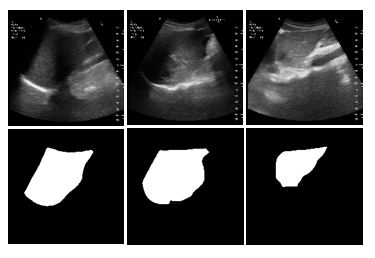

US Liver Segmentation Results: We used FCN [10], UNet [13], UNet++ [20] with EfficientNetB7 encoder, and TransUNet [2] for segmenting US scans for US liver segmentation (Table 1). TransUNet achieved the best Accuracy (Acc.), Dice Score Coefficient (DSC), Intersection over Union (IoU), and Hausdorff distance (HD) for unseen data. This is because TransUNet uses transformers to encode tokenized image patches from a CNN feature map. Thus, the input sequence captures global contexts [2]. We used UNet as the decoder to decode the hidden feature for generating the final segmentation masks. 2D liver predictions overlap well with ground truth liver labels. This, in turn, leads to an accurate liver volume calculation. Ours is the first method that uses a transformer network in US liver segmentation. Following this result, we used TransUNet for all other experiments.

Figure 2: US segmentation and 3D reconstruction results: Three input US sagittal plane images, corresponding segmentations, and 3D liver reconstructions using the shape parameters for three subjects.

Table 1: Segmentation accuracy: TransUNet performs better and, hence, was selected for subsequent experiments. \ast represents the usage of EfficientNet-B7 as an encoder. 3D reconstruction accuracy: CD and MSD are less when we combine TransUNet with Param. Regress. MLP than UNet.

Segmentation FCN UNet UNet++\ast TransUNet

Acc. (%) \uparrow 93.2 95.4 94.4 97.5

DSC (%) \uparrow 38.5 65.6 68.1 91.3

HD (mm) \downarrow 5.5 4.8 4.5 3.6

IoU (%) \uparrow 24.1 50.2 52.7 84.4

Recon. TransUNet UNet

Accuracy + Recon. + Recon.

MSD (mm)\downarrow 6.6 6.8

CD (mm) \downarrow 12.8 13.1